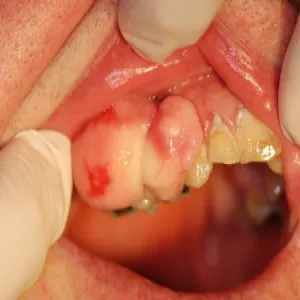

Nadziąślak

Nadziąślak, epulis